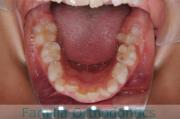

上顎

下顎